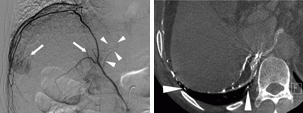

A JVIR feature shows a C-arm computed tomography (CT) scan of the right inferior phrenic artery (RIPA) in transcatheter arterial chemoembolization of patients with hepatocellular carcinoma (HCC).